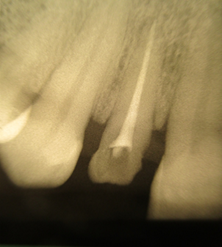

She also exhibits anterior diastemas. The periapical radiograph reveals insufficient endodontic treatment and a periapical lesion (Figure 2).

Figure 2: Preoperative Radiograph.

The level of vestibular damage is slightly subgingival. The prosthetic treatment plan consisted of fabricating a zirconia crown after coronoradicular reconstruc-tion. The patient decided to keep the diastemas. The removal of carious tissue and endodontic retreatment were performed (Figure 3).